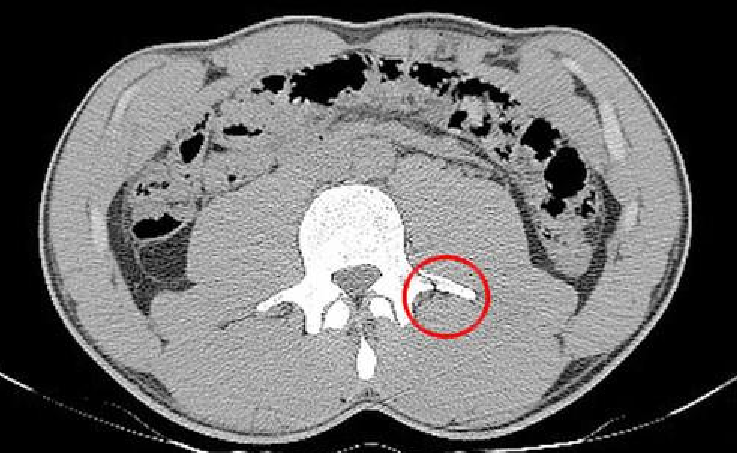

ネイマールが負傷したのは脊椎。身体を支える上で極めて重要な部位であり、負傷の箇所が仮に数cmズレていたら車椅子での生活を強いられていたという報道もある。その後の経過も順調のようで、先日は恋人であるブルーナ・マルケジーニさんと直立した状態で写真におさまっていた。

そんなネイマールの負傷の箇所がモロにわかる写真を、スペイン『SPORT』が独占で伝えている。

赤い丸で囲まれた部位が骨折したと思われる箇所だが、少し確認しづらいのでアップにしてみよう。

パックリ・・・これは痛い。